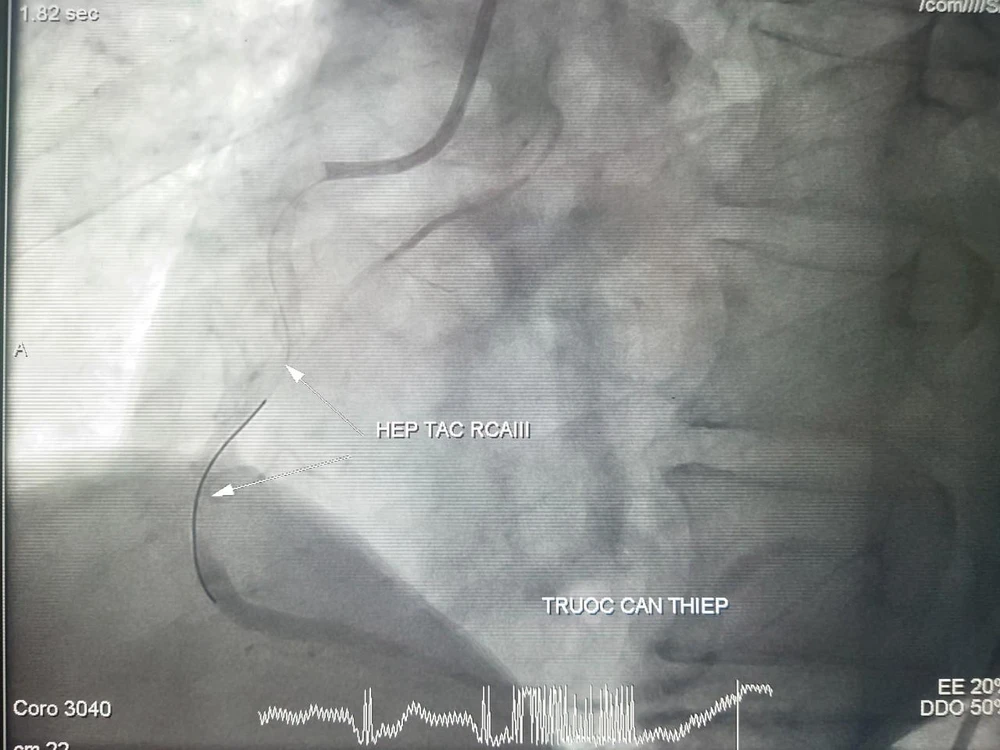

Hình ảnh DSA mạch trước và vành sau can thiệp. Ảnh: BVCC

Tiếp đó, ê kíp chụp và can thiệp mạch vành cấp cứu, kết quả ghi nhận bệnh nhân tắc hoàn toàn RCAII (động mạch vành phải đoạn giữa) và huyết khối. Các bác sĩ đã can thiệp thành công sang thương bằng stent phủ thuốc, kết quả tái thông hoàn toàn mạch vành sau can thiệp sau 20 phút.